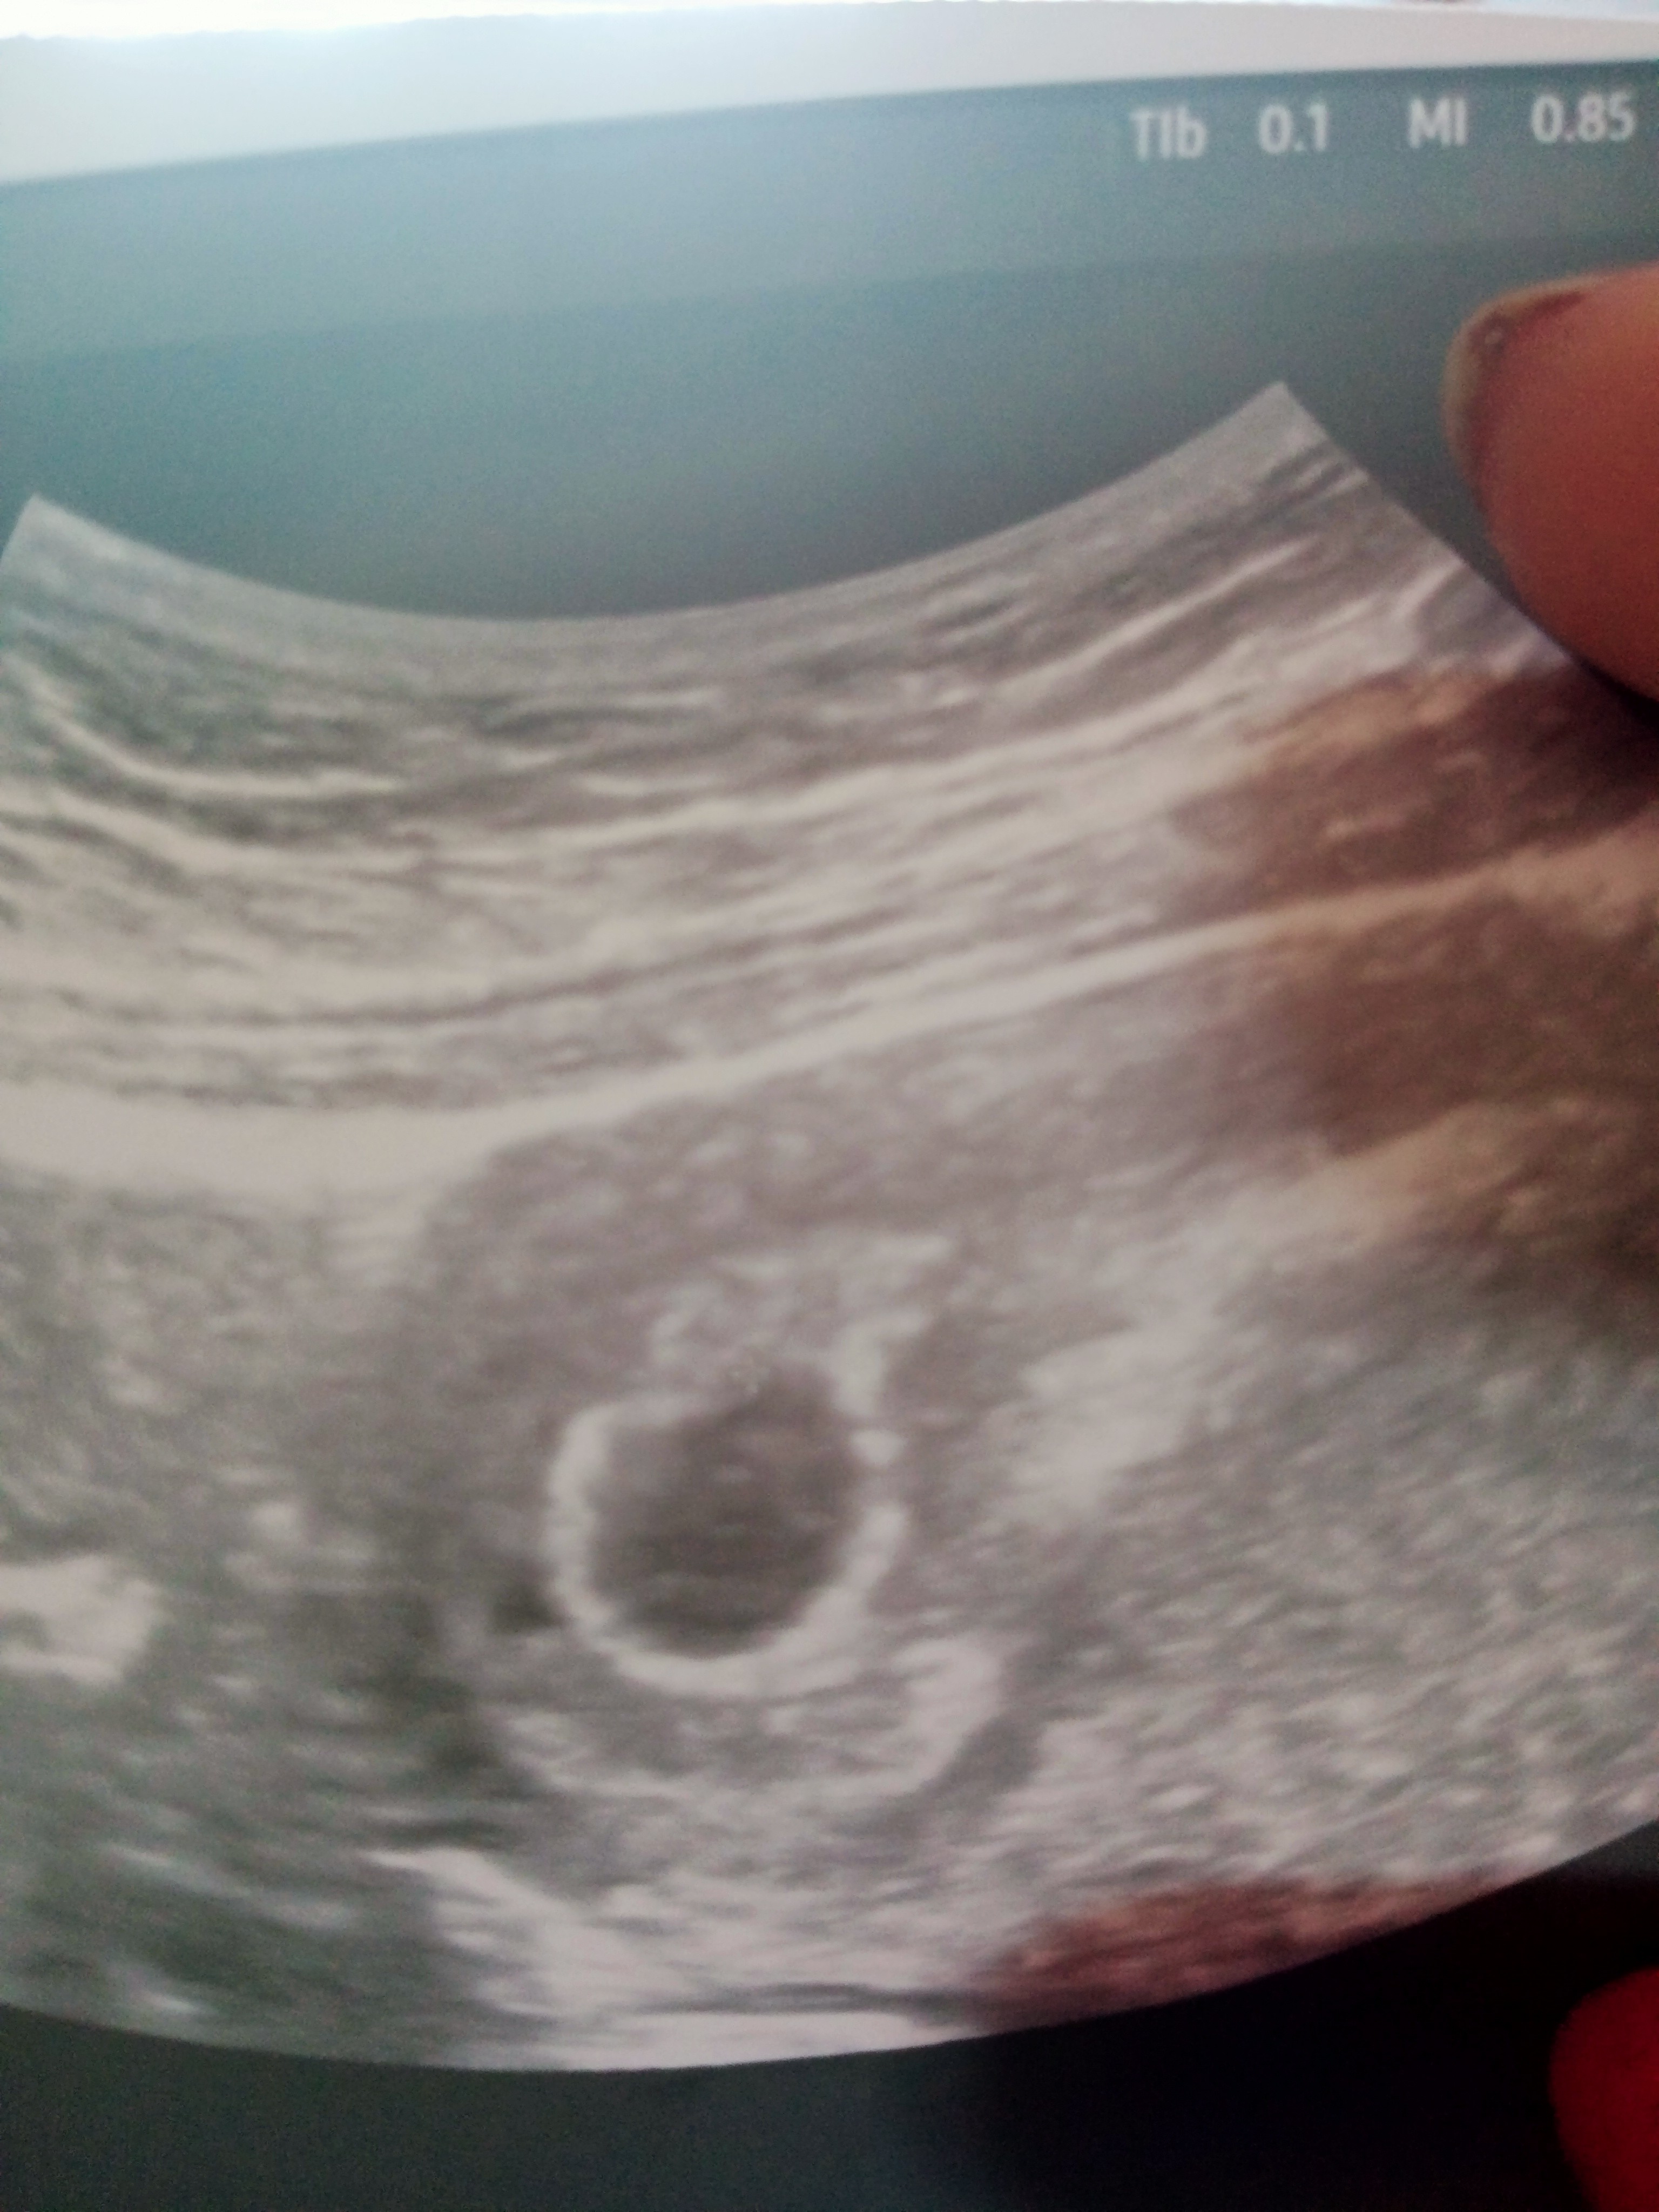

Czy to jest pusty pęcherzyk ciążowy ?

Część dziewczyn czy ja już dostaje schizy czy tylko ja coś tam widzę ? , 26marca miałam miesiączkę , 27 kwietnia zrobiłam test i wyszły dwie kreski słabe , poszłam do lekarza dał mi skierowanie na USG byłam na USG dzisiaj i twierdzi lekarz że albo jest to bardzo wczesna ciąża , pęcherzyk na 12mm albo po prostu jest to pusty , nie mają najlepszego sprzętu , za tydzień mam mieć kontrolne USG , w dodatku napisał tętno płodu wątpliwy co to znaczy to wkocu jest zarodek czy nie ? Dodam że jeszcze napisał że to 4-5 tydzień

Jutro mam wizytę u innego lekarza może lepszy sprzęt i będzie lepiej widać , ja naprawdę mam wrażenie że tam jest zarodek , nawet porównywałam zdj z internetu i jak jest pusty to naprawdę widać że jest czysto a tutaj coś widać przecież

Czyli jeżeli mój pęcherzyk ma 12mm to jest jeszcze jakaś szansa mimo to że nie widać nic że nic , tak twierdzi lekarz.. ja coś tam widzę albo wpadam w schize

Czy tylko ja coś tam widzie ?

Co to jest to w środku wie ktoś .?

Ja uważam ze widać pęcherzyk żółtkowy, po 1-2 dobach od pojawienia się powinien być zarodek. Ale faktycznie sprzęt słaby. Ja mam usg z z 5+2 i nic w środku nie widać, a 5+4 byl pęcherzyk zoltkowy. Sprawdziłabym przyrost bety i progesteron. Teraz jestem w 8+4 i ładny dzidziuś rośnie.